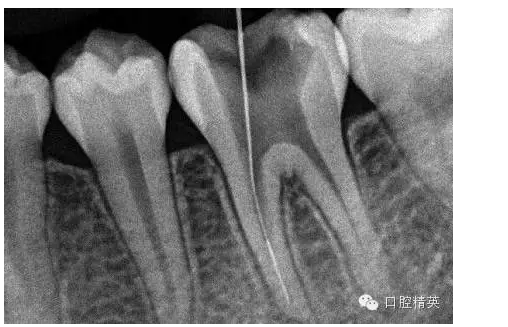

9,斷針取出術(shù)后X-P,RCT待續(xù)。。。